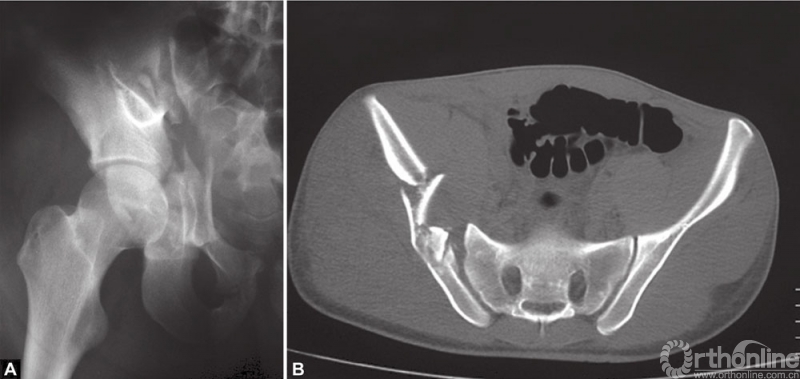

A和B双柱粉碎性骨折合并骶髂关节脱位

上述骨折的轴向断层CT扫描

部分骨折严重粉碎,固定难度大。骨折固定的原则包括:从后向前复位骨折;从髂骨完整的部分向前柱骨折的部分复位,纠正前柱骨折块外旋移位。复位髂骨骨折块时,可以采用钩状复位钳或者将Schanz针拧入髂嵴,当作操作杆,对抗内旋力量,将前柱复位到完整的后柱上。